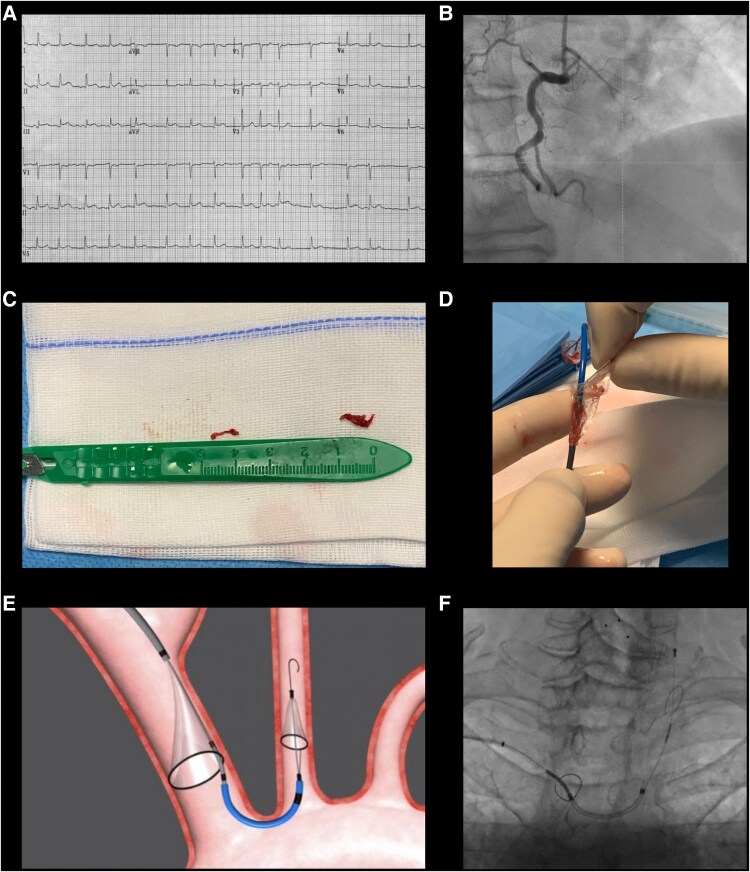

Case presentation: A 73-year-old man presenting with ST-elevation myocardial infarction was diagnosed with impending paradoxical embolism, as a large thrombus was visualized entrapped in a patent foramen ovale. We performed systemic thrombolysis after deployment of a cerebral protection device, which resulted in complete dissolution of the thrombus without major thromboembolic events. Thrombolysis was complicated by development of intracranial haemorrhage that resolved without major neurological sequelae. The patient was discharged on a direct oral anticoagulant.

Discussion: Treatment strategies for impending paradoxical embolism include surgical thrombectomy, percutaneous thrombus retrieval, and systemic thrombolysis. We report for the first time the effective use of a cerebral embolic protection device to reduce the risk of ischaemic injury to the brain during systemic thrombolysis.